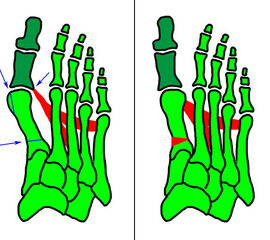

Klinisches Erscheinungsbild eines Hallux varus (eigenes Bildmaterial)

Abbildung 1

Bei einer geringgradigen Ausprägung eines Hallux varus (bis ca. 10° negativer Hallux-valgus-Winkel) sind die Betroffenen selten beeinträchtigt, in der Regel bedarf es keiner Therapie. Die Korrektur durch den Druck der Zehenkappe im Schuh ist meist bereits ausreichend.

Bei zunehmender Fehlstellung klagen die Patienten über Druckbeschwerden im Schuh, insbesondere am Endglied innenseitig oder über dem IP-Gelenk der Großzehe sowie über bewegungsabhängige Schmerzen im 1. MTP-Gelenk. Häufig sind die Betroffenen auch kosmetisch unzufrieden (Janis et al., 1975).